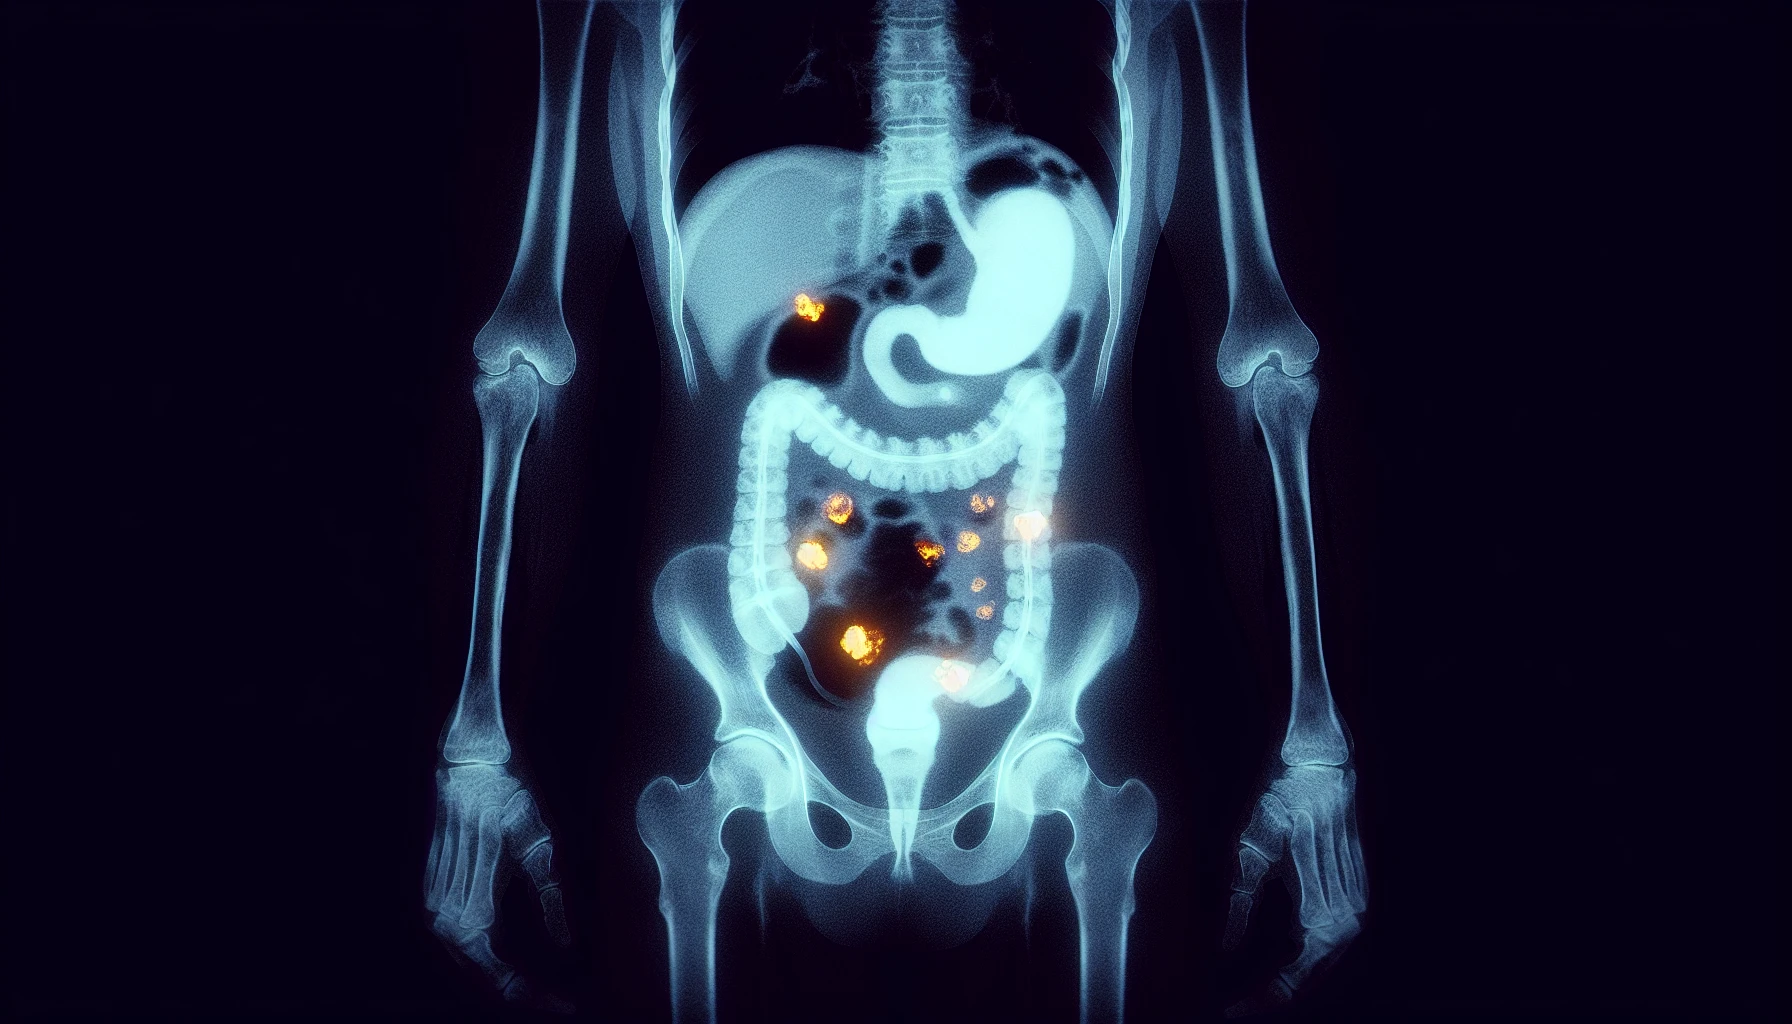

Positron emission tomography (PET) scans have risen to prominence as a key tool in the detection and management of colorectal cancer. By providing comprehensive mapping of glucose metabolism throughout the body, PET scans offer accurate information on tumor recurrence, metastasis, and therapy response. This functional imaging technique has had a significant effect on the evaluation of patients with colorectal carcinoma (CRC), particularly in identifying formerly undetected sites of metastatic disease, patients with an increasing carcinoembryonic antigen (CEA), and local recurrence.

As noted in the Journal of Nuclear Medicine, FDG PET/CT is a significant imaging modality in the clinical management of colorectal and anal cancer patients. The combination of FDG PET and computed tomography (CT) has proven advantageous in detecting colorectal cancer metastases and local recurrence that may be otherwise unseen. By offering a more comprehensive view of the disease, PET scans have the potential to improve patient outcomes and guide treatment decisions.

Furthermore, PET scans provide valuable information on the metabolic activity of cancer cells, allowing for more precise tumor visualization. This is particularly important in colorectal cancer, where metabolic activity can be an indicator of tumor aggressiveness and potential response to therapy. By incorporating PET scan findings into patient management, healthcare professionals can better assess the disease and develop a more tailored treatment plan for each individual patient.

PET scans prove their efficiency in identifying liver metastases in colorectal cancer patients, enhancing surgical decision-making and patient outcomes. With a sensitivity of 94.1% for detecting hepatic metastases from colorectal cancer, PET scans offer a high degree of accuracy in identifying liver metastases. This information is crucial for healthcare professionals as they determine the most appropriate treatment options for each individual patient.